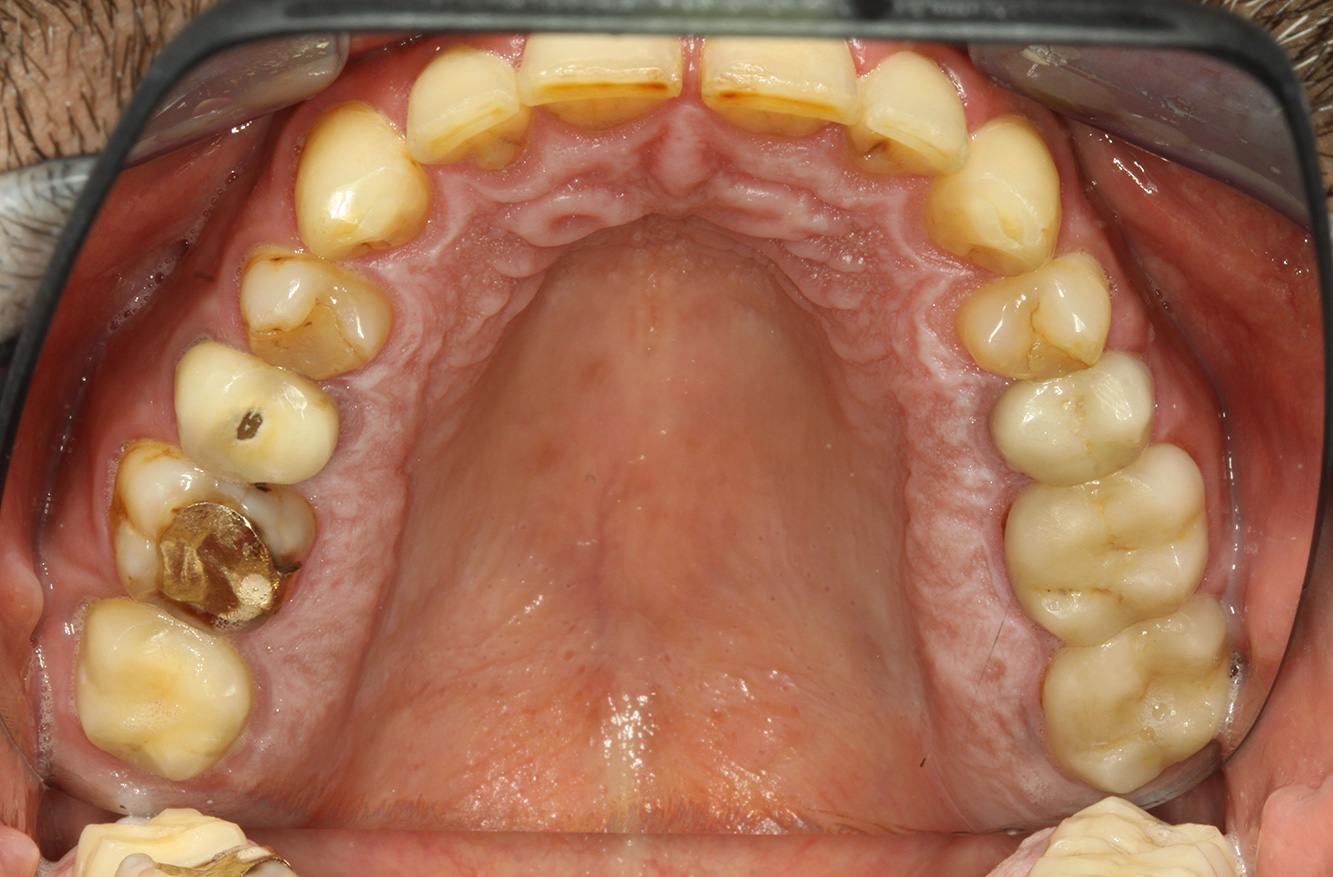

Paciente con endocarditis con lesiones de caries activas*

Fotos: © Dr G. Schmalz y Dr D. Ziebolz MSc

El paciente tiene 39 años con valvuloplastia frente a una insuficiencia valvular y endocarditis. Toma regularmente ASS 100 (ácido acetil salicílico) como anticoagulante. En el ámbito del estilo de vida, la alimentación se identifica como promotora de caries, ya que suele consumir alimentos azucarados y seis o siete comidas al día. La salud oral del paciente muestra un riesgo medio de caries con lesiones activas. El riesgo de periodontitis es bajo, presenta gingivitis. Se hacen las siguientes recomendaciones para el tratamiento profiláctico.